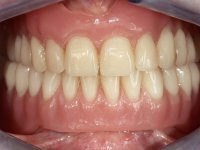

Female patient, 57 years-old, non-smoker, with a full denture in the maxilla and a removable partial denture in the mandible. Teeth 43-41-41-31-32 were indicated for extraction. Posterior sectors of the mandible presented significant bone resorption.

After clinical and radiological evaluation several rehabilitation plans were discussed with the patient. It was decided to extract the remaining lower teeth and do an overdenture retained by two dental implants with the locator attachement system to achieve a better retention and stabilization of the lower denture.